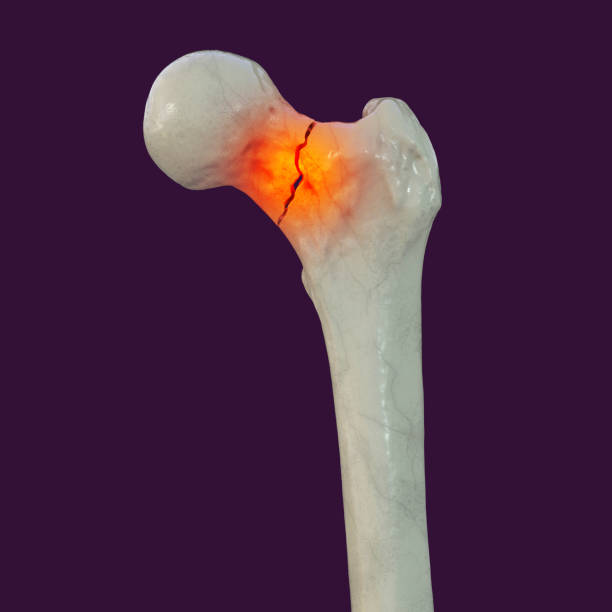

Fréquente chez les patients âgés ostéoporotiques après chute. Urgence chirurgicale dont le traitement dépend du déplacement, de l'âge et de l'état général.

Ostéosynthèse ou prothèse

Fractures du fémur proximal (col fémoral, massif trochantérien) chez les patients jeunes ou fractures peu déplacées, permettant de préserver la tête fémorale.

L'opération

Fixation interne par vis cannulées, clou gamma ou lame-plaque selon le siège et le type de fracture. Prise en charge en urgence chirurgicale.

Nécrose avasculaire de la tête fémorale, pseudarthrose, infection.

Consolidation en 3 à 6 mois selon le type de fracture.